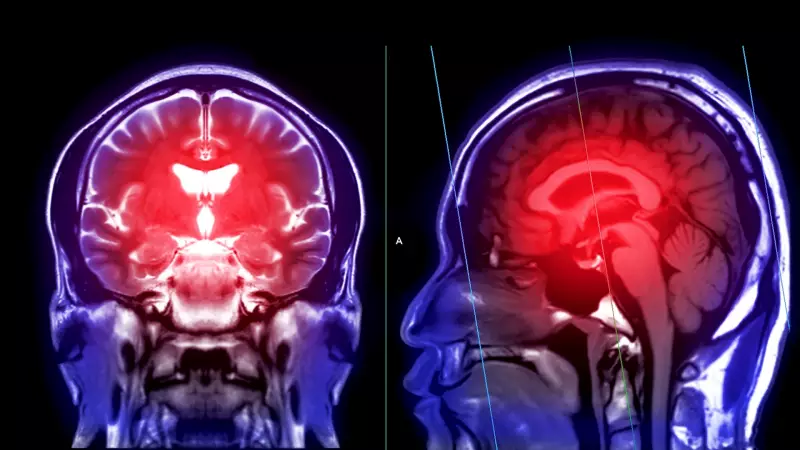

Şaşırtıcı ama gerçek: İnme artık sadece yaşlıların sorunu değil. Son veriler, genç yetişkinler arasında inme vakalarının endişe verici bir hızla arttığını gösteriyor. Eskiden 'yaşlılık hastalığı' olarak bildiğimiz bu durum, şimdilerde 20'li ve 30'lu yaşlardaki bireyleri de tehdit ediyor.

Uzmanların dilinden düşürmediği bir uyarı var: "Genç olduğunuz için güvende değilsiniz." Öyle ki, son on yılda genç erişkinlerde görülen inme oranları neredeyse %15 artış göstermiş durumda. Bu rakamlar, sağlık otoritelerini harekete geçmeye zorluyor.